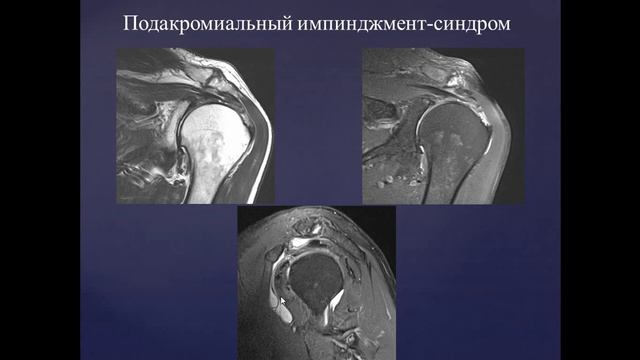

прямой эфир с Романом Вадимовичем Бартеневым @orthodoc.md - врачом ультразвуковой диагностики, ортопедом-травматологом, мануальным терапевтом, специалистом по скелетно-мышечной боли и физической реабилитации. Тема прямого эфира: «МРТ. Зачем это исследование?» Руководитель проекта - Касаткин М.С. @dr.kasatkin вместе с нашим гостем обсудит следующие вопросы: какой смысл МРТ в современном мире; нужно ли знать МРТ массажисту и тренеру; все ли врачи понимают МРТ; МИФЫ об МРТ. https://www.instagram.com/kineziocourse/ КИНЕЗИОТЕЙПИРОВАНИЕ ОБУЧЕНИЕ https://www.instagram.com/orthodoc.md/ Бартенев Роман Вадимович ОРТОПЕД, МАНУАЛЬНЫЙ ТЕРАПЕВТ https://kinesiocourse.getcourse.ru/mri ОНЛАЙН КУРС МРТ КОЛЕННОГО СУСТАВА